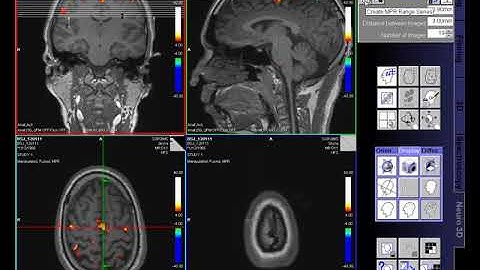

Uncovering the Topology of Time-Varying fMRI Data using Cubical Persistence (spooky version)